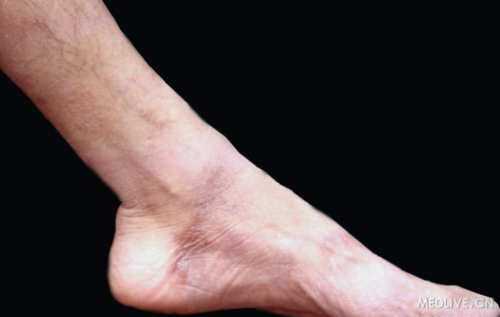

足部麻风-腓浅神经粗大

足部麻风-腓浅神经损害引起足下垂